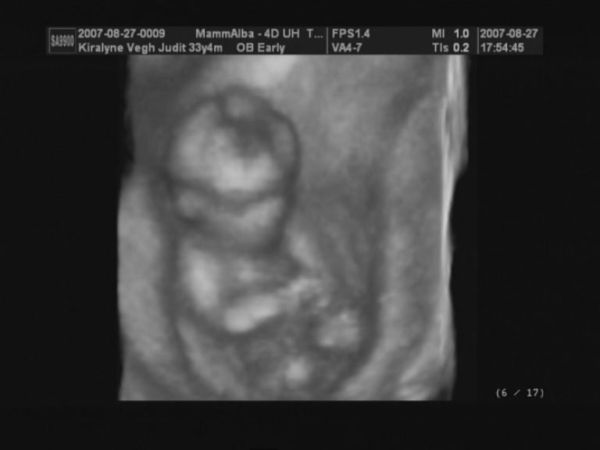

Judy, nagyon szép babátok van, gyerekek mit szóltak???